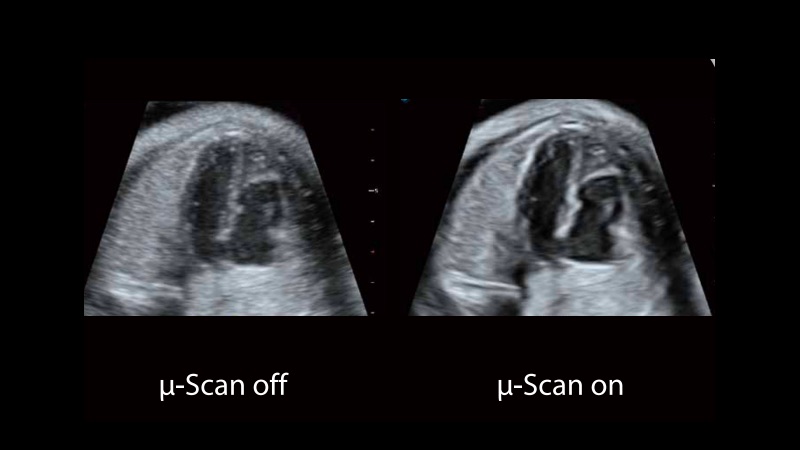

μ-Scan+新一代微米成像技術(shù)

新一代微米成像技術(shù)大大提高了器官和病變的可見(jiàn)性。高清對(duì)比度分辨率將抑制斑點(diǎn)噪聲,同時(shí)保持真實(shí)的組織結(jié)構(gòu)。